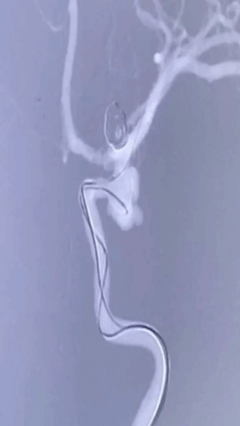

NUMEN Case 2